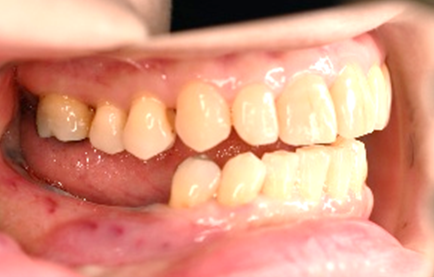

治療内容

レントゲンで詳しく診てみると、左下の動いている歯、右下の一番奥は、保存することができず、抜歯しました。左下の抜歯したところは、骨造成後、左に2本、右に2本インプラントを埋入しました。

所感

左下の抜歯したところは、大きく骨が欠損していましたので、骨造成をしました。5か月間待ってからインプラントを埋入しました。骨をきちんと作ってから埋入して、正解でした。今回もX-Guideを使った埋入で、安心安全に行うことできました。